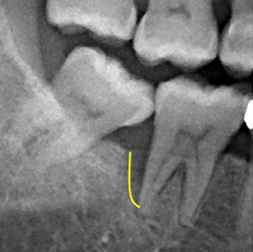

检查:患有严重牙周病问题,牙结石堆积,右下第七颗大臼齿齿槽骨严重流失

黑影区域为齿槽骨被牙结石及细菌严重侵蚀,齿槽骨被细菌侵蚀后的高度显示出骨头降低程度至牙根尖处。

齿槽骨已长回80%,復塬状况良好齿槽骨内的骨头逐渐生长,骨头高度比治疗前高出甚多。